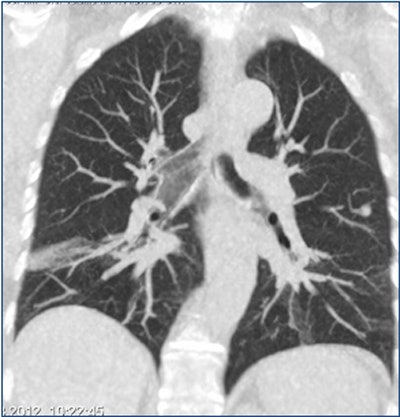

| Above is a false-negative chest x-ray. Below, an ultralow-dose 3-mm axial chest CT of the same patient acquired on a 320-detector-row scanner (Aquilion, Toshiba) and reconstructed with AIDR 3D shows a 7-mm nodule. At bottom, the coronal maximum-intensity projection shows a 7-mm nodule in the left lung and some atelectasis in the right lung. All images courtesy of Dr. Trond Aaløkken. |